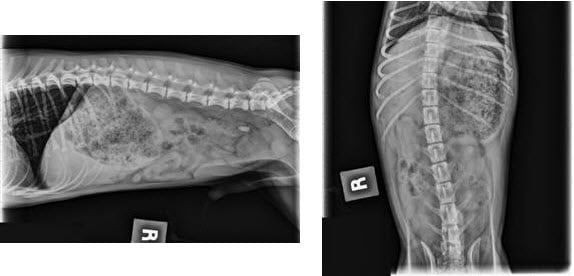

These two radiographs are of a dog with an obstructive Gorilla Glue mass in his stomach. (Images courtesy of Dr. Garret Pachtinger, VMD, DACVECC).